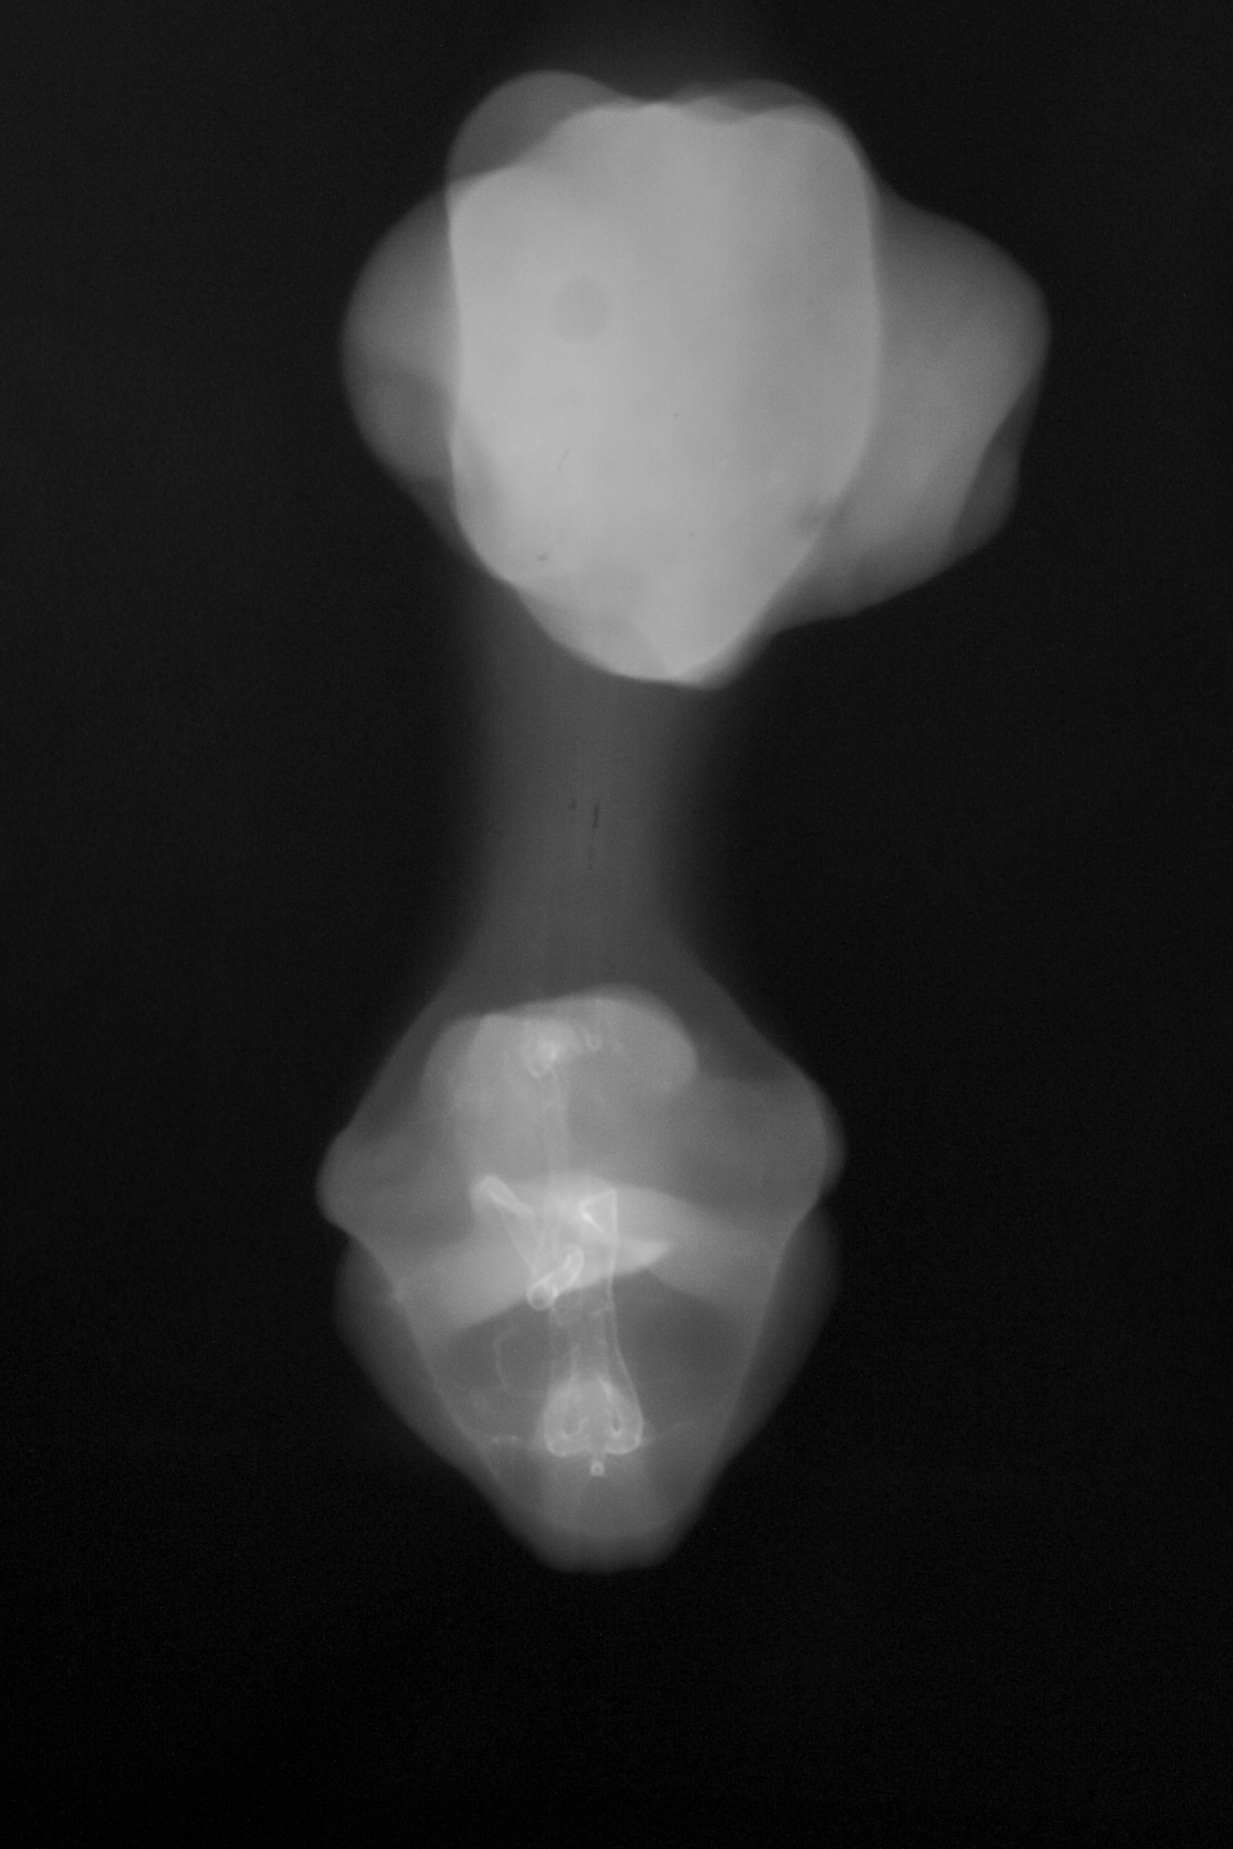

Chick Embryo Microangiography

Hamburger-Hamilton (HH) Stage 30 (approx. 6.5 days)

X-Ray Micrographs